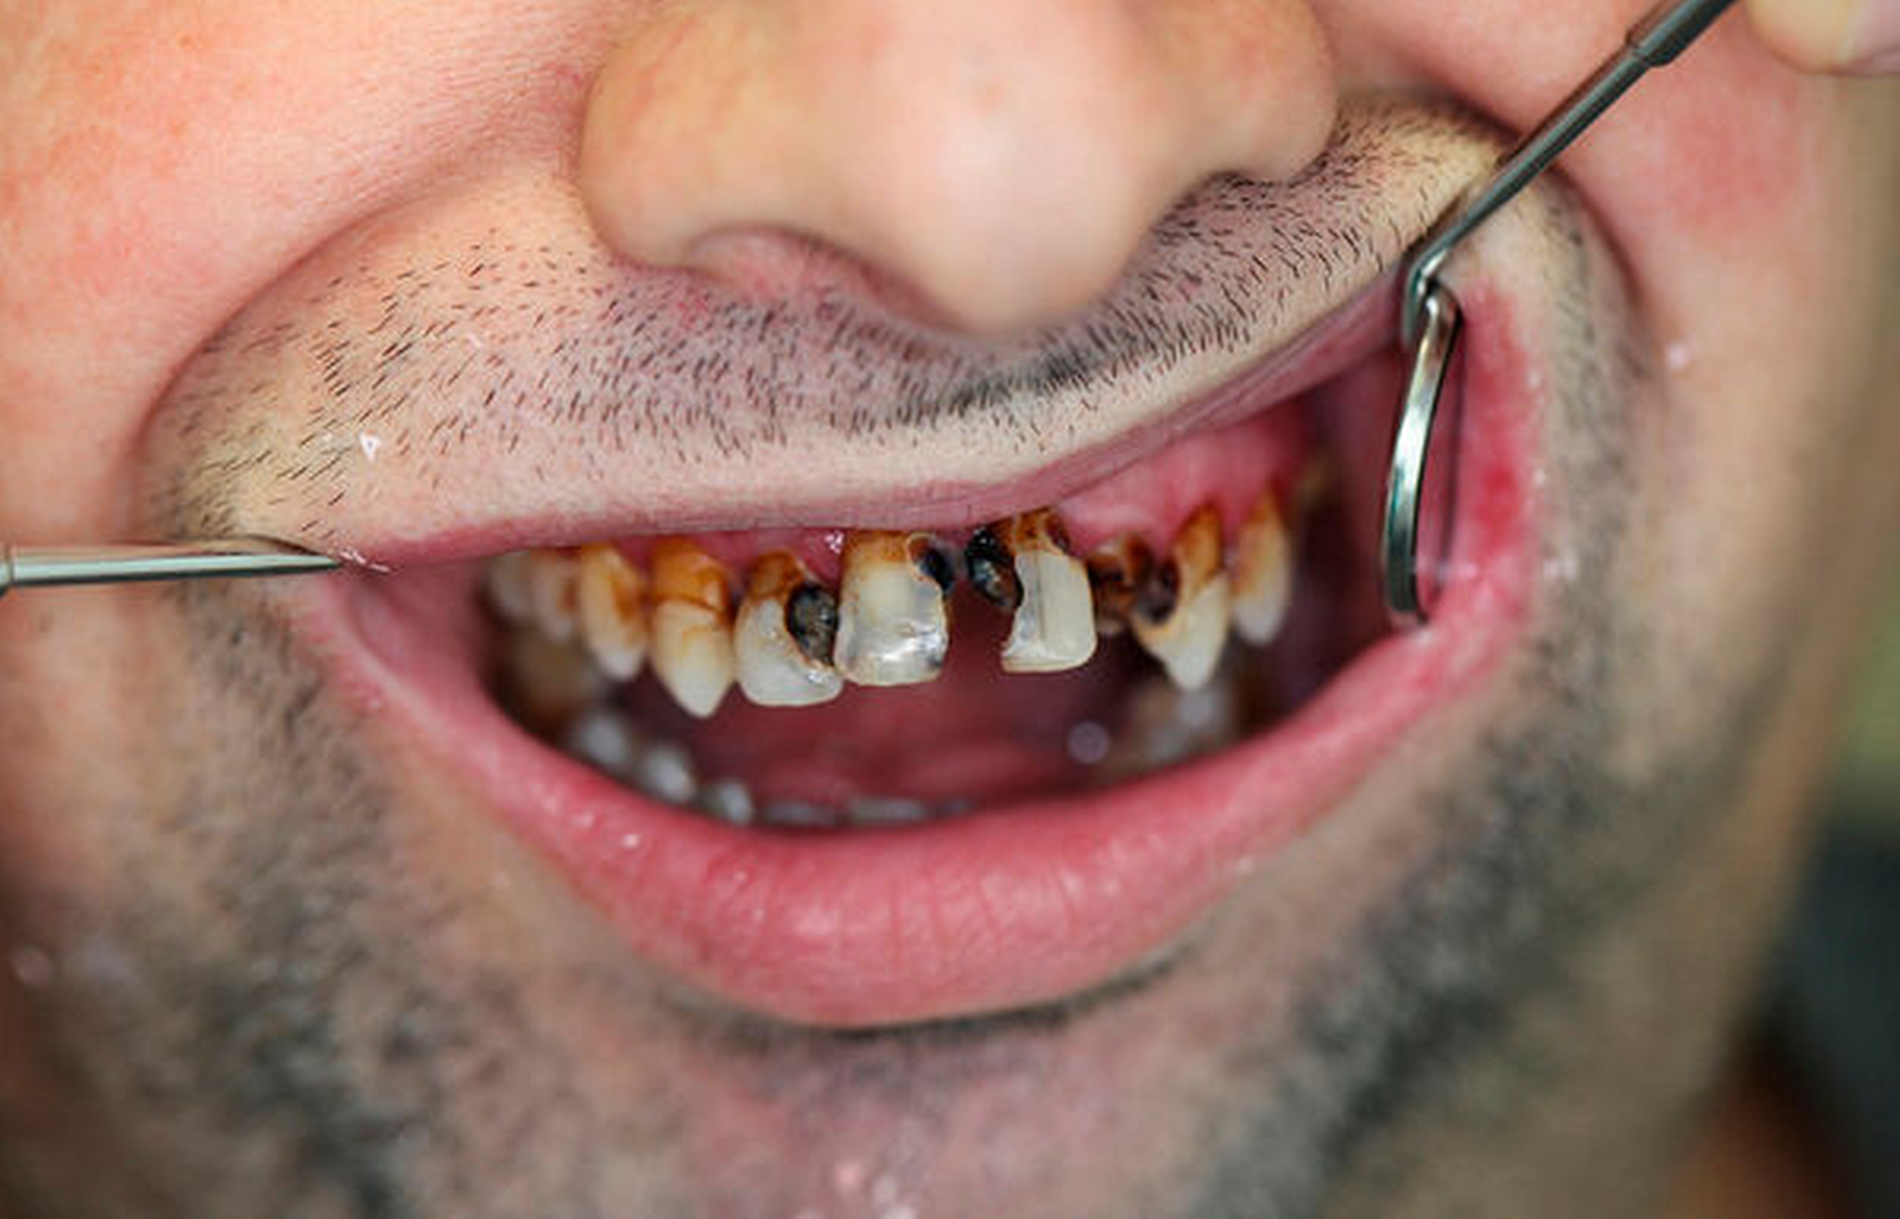

Im August 2019 stellte sich ein 37-jähriger Patient in der ambulanten Sprechstunde der Mund-, Kiefer- und Gesichtschirurgie der Universitätsmedizin Mainz nach Überweisung durch seinen Hauszahnarzt und der Bitte um Therapieübernahme bei notwendiger Zahnsanierung vor. Bei der klinischen Untersuchung zeigte sich eine ausgedehnte Sanierungsbedürftigkeit der Zähne bei skelettaler Klasse II mit 7 mm Distalbisslage und einer mit 1 cm maximalen Schneidekantendistanz (SKD-max.) stark eingeschränkten Mundöffnung (Abbildung 1). Nebenbefundlich litt der auf Unterarmgehstützen angewiesene Patient bei einem Körpergewicht von 120 kg und einer Körpergröße von 170 cm an einer Adipositas per magna (BMI > 40), belastungsabhängiger Dyspnoe und einem obstruktiven Schlafapnoesyndrom bei verkleinertem posteriorem „airway space“, was den Patienten zum Schlafen in aufrechter Position zwang.